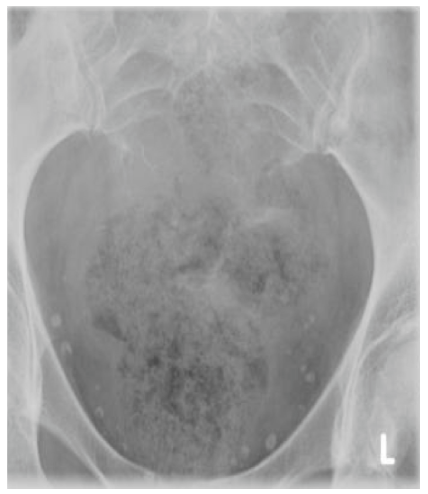

Radiographic imaging is used to help form a diagnosis of Chordoma. These include X-Ray, MRI, CT and Bone Scans.

An example of an X-ray is shown.